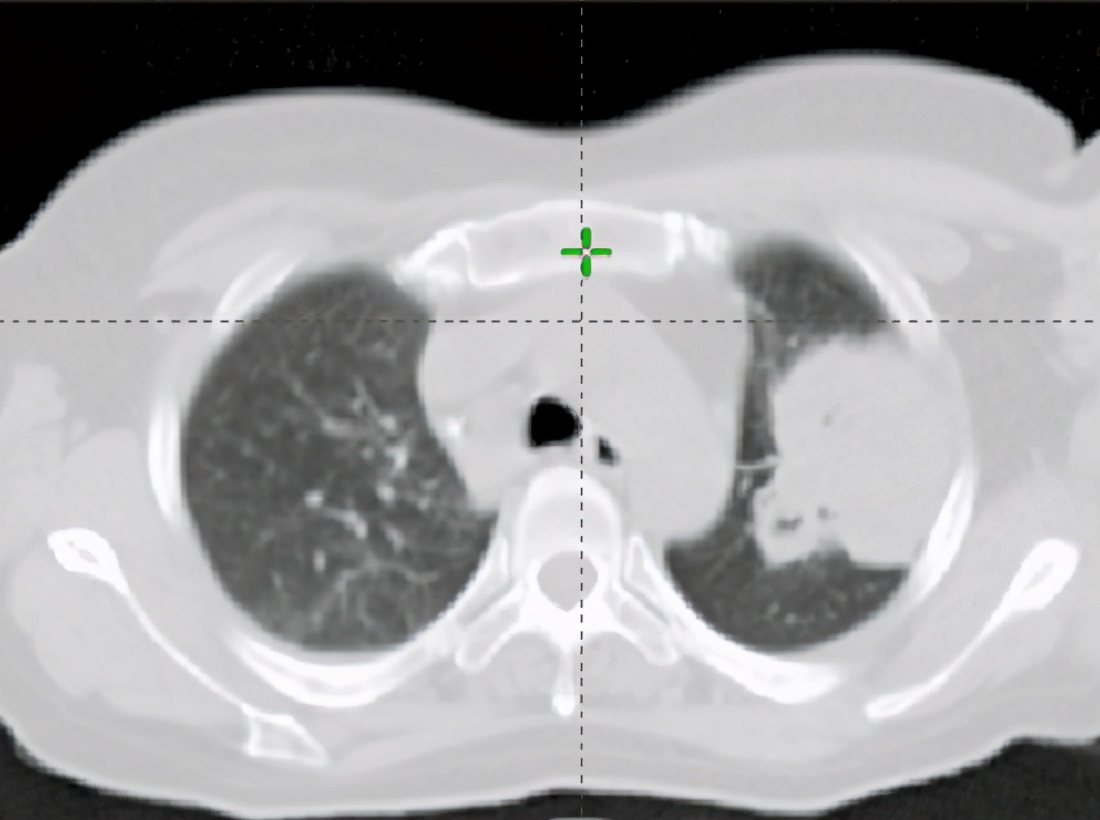

2020年8月,患者找到哈医大一院肿瘤一科主任张大昕教授,诊断为晚期肺腺癌、多发脑转移、多发淋巴结及脏器、软组织转移。

坚持治疗2个周期后,患者复查结果提示病情稳定无进展,这就意味着新的治疗方案有效了。在那段最难熬的日子里,医护人员经常在患者半夜无法安睡时跟她聊天,鼓励她积极应对生活。目前,患者的身体状况已趋于正常,只需定期回医院治疗并定期复查。